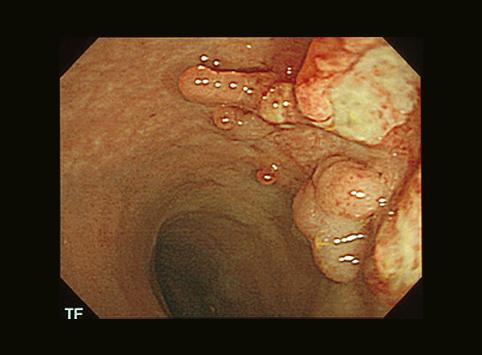

Cáncer Precoz a Células Endocrinas, tipo IIa+IIc, crecido en Colon Signoides

Tokyo Pref., Centro Nacional de curaciones de Cáncer, Hospital Central y Centro Kyusyu de Curaciones de Cáncerc

Tumor Epitelial Maligno/Otros

colon/sigmoides

Endoscopia

Tipo 0(tipo superficial)/Tipo IIa(IIa+IIc)

15 - 19

sm